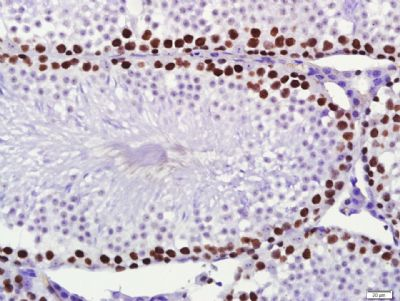

一抗:Anti-PCNA (bsm-33035M)

使用IHC003试剂盒

组织/细胞:小鼠睾丸